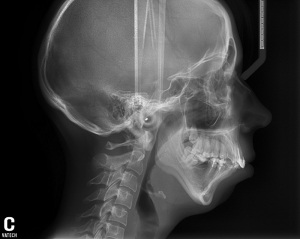

Гениопластика подбородка при отсутствии подбородка

Добрый день, проконсультируйте можно ли в моем случае обойтись "малой кровью" исправить дефект с помощью гениопластики.

Врач говорит прикус компенсирован.

Все снимки прилагаю.

Установка импланта радикально изменит ситуацию к лучшему. Помимо улучшения черт лица, значительно изменится боковой контур шеи, уйдет второй подбородок

Но "компенсированный" прикус не исключает, при такой картине, проблем с височно-нижнечелюстным суставом.

Для камуфлирующего эффекта (для уменьшения степени микрогнатии), действительно, можно установить имплантат подбородка. Для полного исправления данного дефекта необходимо обратиться к челюстно-лицевому хирургу для более сложной реконструктивной операции.